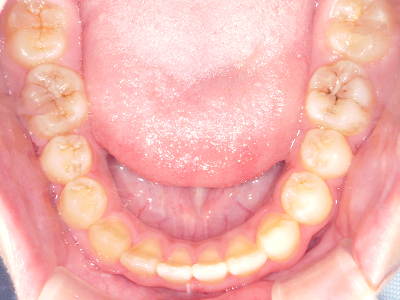

歯並びの相談に来られるお子様は、口呼吸をしているケースが多く、これが歯並びに大きな影響を与えています。

↓ - 下あごが狭くなる・下あごの位置が悪くなる

↓ - さまざまな不正咬合が生じる

ないき歯科クリニックでは、上あごの成長不足を補い、鼻呼吸を獲得しつつ歯列を整え、将来のお口をより健康な状態にすることをゴールに定める矯正治療をおこなっています。